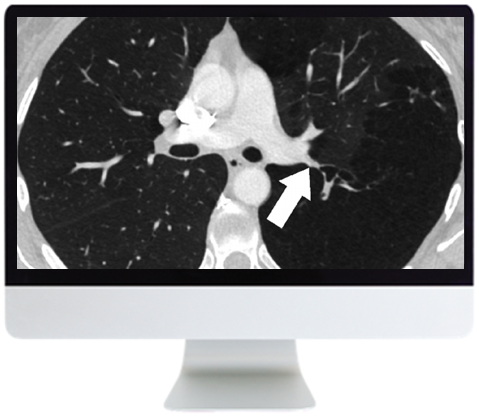

- ARRS Basic Chest Imaging 2019 (CME VIDEOS) This course covers basic topics in thoracic imaging, a rapidly evolving subspecialty. Course content provides a focused review of basic chest imaging topics, as well as important updates regarding thoracic disease entities and technological advancements. Topics include imaging of airways, imaging of atelectasis, imaging of infections in immunocompromised hosts, current concepts and approach to management of pulmonary nodules, as well as imaging of pulmonary embolism.

- Management of Solid Pulmonary Nodules: Characterization and Update—J. Ko

- Adenocarcinoma and the Subsolid Nodule: Current Concepts—J. Ko